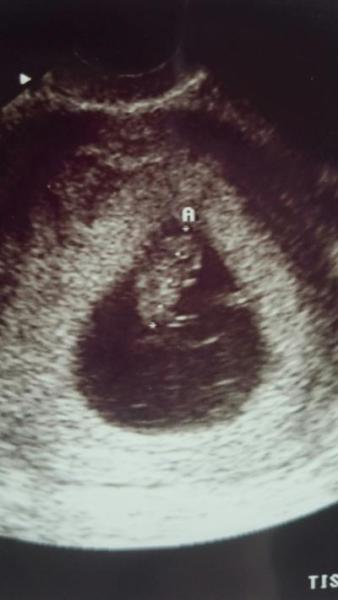

Nun zu dem kleinen Racker, heute 8+0 ist er 1,5 cm groß und das Herzchen pochert. Ein Foto ist im Anhang, Kopf oben und schaut nach rechts, das ärmchen rechts und etwas beinchen kann man auch ganz gut erkennen